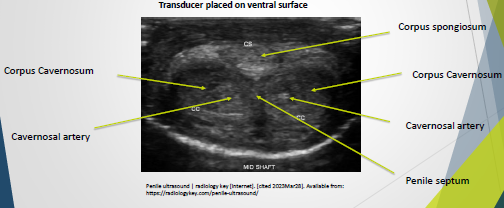

Imaging (Transverse)

Technique:

Place the transducer on the ventral surface at the level of the glans.

Move down to the base of the penis to complete a survey in the transverse position.

Take images at various intervals from the base, mid-shaft, and distal regions of the penis.

Corpus spongiosum is easily compressed.

Use extra gel to alleviate compression.